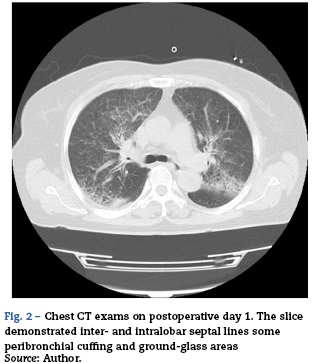

Saturation of peripheral oxygen (SpO2) and end-tidal carbon dioxide concentration (ETCO2) were also continuously monitored. The operation time for the procedures was 99 min. Fluid balance was 1290 ml. No transfusion was performed. During the operation, the patient's haemodynamics were stable with blood pressure of around 120/80 mmHg and 3.5-IL/min of cardiac output. Respiratory condition was also stable; however, SpO2 was slightly decreased as the end of operation neared. Immediately after the operation, she was returned to the supine position and her trachea was suctioned; however, only a small amount of frothy sputum was observed. Simultaneously, she regained consciousness and spontaneous breathing was sufficient, then the tracheal tube was removed and she was transferred to the intensive care unit (ICU). After admission to the ICU, she remained alert and neuro-logically unchanged. Oxygen was administered by facemask at 6Lmin-1; however, her SpO2 showed 90-96% and PaO2 was 89 torr with deep breathing urged. She never complained of dyspnoea no matter how many times we asked although she were coughing up and spitting out. Her haemodynamics was stable throughout the ICU stay. Transthoracic echocardiogram showed normal left ventricular function and normal chamber size. On the next day, her bladder temperature was 37.1 °C. Inflammatory markers, such as C-reactive protein (CRP) and white blood cell (WBC) counts, were 1.3 mg/dl and 11,000/[xl with prophylactic administration of cefazolin 2 g/day for surgical site infection. Presentation of active pneumonia seemed negative. However, a chest X-ray taken on that day, which showed bilateral marked prominence of the interstitial lines, were consistent with pulmonary oedema (Fig. 1). A subsequent CT exam, which demonstrated inter- and intralobar septal lines some peribronchial cuffing and ground-glass areas, confirmed the diagnosis of pulmonary oedema (Fig. 2).